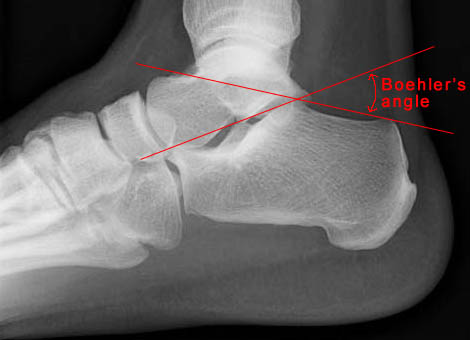

Lateral view of ankle showing Boehler's angle

• Boehler's angle is defined as the angle formed by two lines: one drawn tangent to the superior aspect of the calcaneus and the second drawn tangent to the inferior aspect of the calcaneus. The angle normally ranges from 20 to 40 degrees.